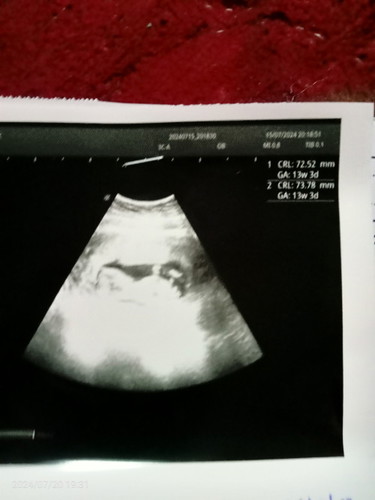

ถามแม่ช่วยดูอายุครรภ์หน่อยค่ะ

แม่ๆว่าอายุครรภ์ประมาณกี่วีคคะ หมอบอกว่า 13วีค แต่เห็นเหมือนเป็นรูปเป็นร่างแล้วนะคะ

13วีค3วันค่ะ